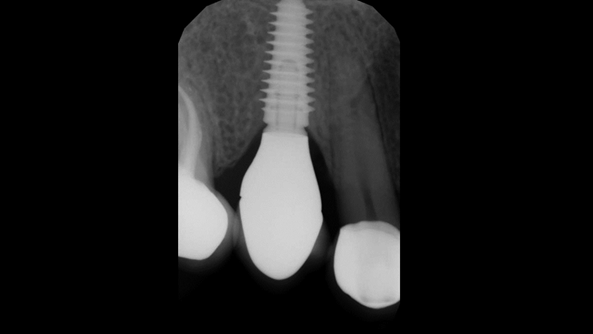

Clinical case: Extraction, immediate implant placement, & provisionalization

- Courtesy of Dr. Iulian Filipov, Romania -

AnyRidge, R2GATE, guided surgery, immediate placement, immediate provisionalization, initial stability, Dr. Iulian Filipov, #25, maxillary posterior, immediate loading, Mega ISQ

Products:

AnyRidge implant system, R2GATE, MEGA ISQ, Digital prosthesis